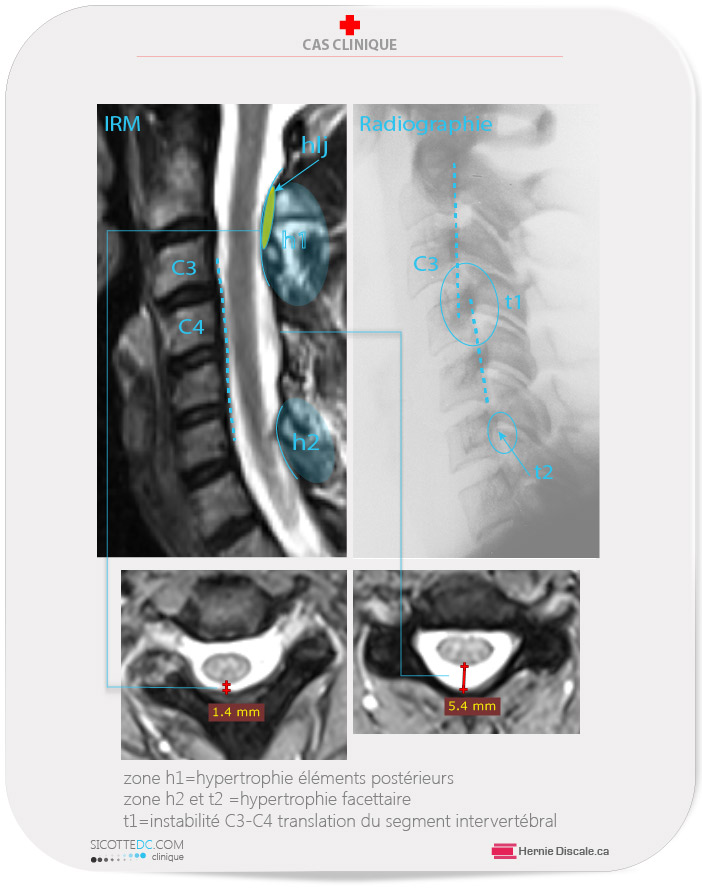

L’imagerie prescrite à notre clinique révèle les caractéristiques suivantes. La radiographie démontre une instabilité de 3 mm (t) entre les segments C3 et C4. On peut apercevoir de l’arthrose facettaire (spondylarthrose) au niveau de C6-C7. Les signes radiologiques sont très subtils à ce niveau (t2) et ne démontrent aucunement l’effet sur les tissus mous. L’IRM démontre l’empiètement des régions (h1 et h2) sur le diamètre du canal spinal. La région h1 a été affectée par l’instabilité cervicale de C3-C4, ce qui a entraîné une hypertrophie du ligament jaune. La région h2, elle, a subi une dégénérescence facettaire typique d’une colonne cervicale sténosée.

Le système de Kang classe la patiente à un grade 1 de sténose spinale.